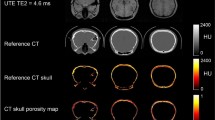

Three different image contrasts were generated using the acquired MR data: MRsimCT38, –log(short TE)39, and short TE–long TE38 (Fig. 1, Supplementary Figs. 1, 2). Qualitatively, all three contrasts preserved the overall skull shape, size, and thickness. Of the three options, MRsimCT achieved the most similar skull density ratio (SDR) as the CT, followed by –log(short TE), then short TE–long TE. SDR is a measure of skull homogeneity, with a value of 0 signifying low homogeneity and a value of 1 signifying high homogeneity. Changes in SDR compared to the CT suggest that bone composition information was lost.

CT contrast of the skull compared to various MR contrasts (skull A). Cortical and trabecular bone contrast is clearly depicted by CT and may be preserved by two of the three MR post-processing methods. The units for MRsimCT, –log(short TE), and short TE–long TE are not the same, thus different windowing and leveling were used. Scale bars and skull density ratios (SDRs) are shown at the bottom of each image. MRsimCT was the preferred choice based on bone contrast, minimal SDR change compared to CT, minimal background signal bias, and generalizable post-processing. Therefore, it was used for the remainder of this study.

Amongst the three MR contrasts of MRsimCT, –log(short TE), and short TE–long TE, MRsimCT was the preferred choice based on bone contrast, minimal SDR change compared to CT, and minimal background signal bias (Fig. 1, Supplementary Figs. 1–3). Background signal bias was due to RF transmit and receive nonuniformities, coil sensitivities, and/or coil shading. Although –log(short TE) also preserved some bone contrast, the remaining background bias would be a source of error when mapping from image values to acoustic properties. The residual background bias may be an artifact of the bias correction algorithm39 because it was observed in both ex vivo and in vivo images39. Furthermore, the bias correction algorithm required substantial parameter tuning to yield sufficient efficacy with the input images. Therefore, it may need to be tailored to each set of MR acquisition parameters. In contrast, the computation of short TE–long TE can be done rapidly, though it also exhibits residual background signal bias (Fig. 1, compare the anterior and posterior portions of the skull). Unlike the other two options, MRsimCT images exhibit minimal background signal bias likely because of its post-processing: